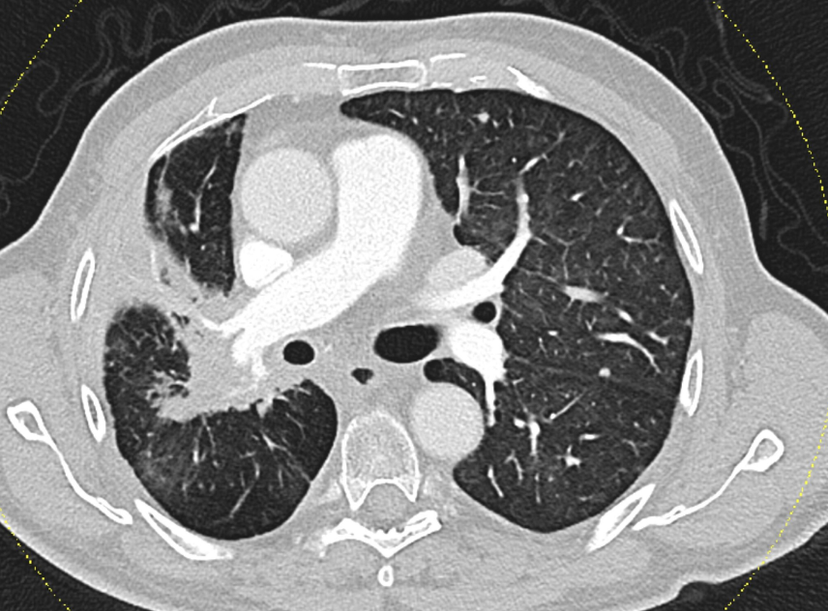

Higher-than-usual doses of radiation in the treatment of inoperable lung cancer can be safely combined with immunotherapy without increasing the risk of severe lung inflammation (pneumonitis). This is the key finding of a recent study conducted by Karl Landsteiner University of Health Sciences (KL Krems). Patients who received 70 Gy of radiation – a dose above the conventional protocol – prior to treatment with the immune checkpoint inhibitor Durvalumab did not develop pneumonitis more frequently than those given a lower dose. At the same time, preliminary data suggest a significant survival benefit. The findings, based on a retrospective evaluation of nearly 40 patients, suggest that more intensive radiotherapy may offer improved outcomes without compromising safety in selected cases.

Lung cancer remains one of the most common and deadliest forms of cancer worldwide. For patients with inoperable stage III non-small cell lung cancer (NSCLC), the established standard of care is concurrent chemoradiotherapy (CCRT) followed by immunotherapy with Durvalumab – particularly for tumours that express the PD-L1 protein, which enables cancer cells to evade the body’s immune defences. However, both radiotherapy and immunotherapy are known to carry a risk of inducing pneumonitis. As a result, total radiation doses have traditionally been limited to 60 Gy (Gray, the unit of absorbed radiation dose). Researchers at KL Krems set out to investigate whether higher doses – which could potentially lead to better tumour control – could be administered without increasing the risk of serious side effects.